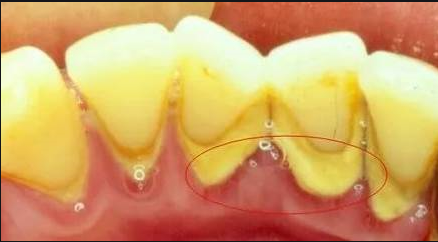

牙結石,又稱牙石,是由食物殘渣、口腔細菌及其代謝產物在牙齒表面(尤其是牙頸部和牙縫處)礦化沉積而形成的堅硬物質。它通常呈黃色或棕色,附著在牙齒上,不僅影響美觀,更對口腔健康構成嚴重威脅。

牙結石的形成是一個漸進的過程。初期,口腔中的細菌會與食物殘渣結合,形成軟垢,如果不及時清潔,這些軟垢會在口腔內環境的作用下逐漸鈣化,最終形成堅硬的牙結石。隨著時間的推移,牙結石會不斷增厚,并向牙齦下方延伸,對牙周組織造成壓迫和刺激。

二、牙結石對牙齦萎縮的影響

牙齦萎縮是指牙齦邊緣向牙根方向退縮,使牙根暴露出來的現象。牙結石是導致牙齦萎縮的主要原因之一。當牙結石附著在牙齒表面時,它會不斷刺激牙齦,導致牙齦發炎、紅腫、出血等癥狀。長期以往,牙齦組織會因受到持續性的機械刺激和炎癥損傷而發生退縮。

此外,牙結石還會為細菌提供一個理想的生存環境,進一步加劇口腔炎癥。這些細菌會釋放毒素,破壞牙周組織,包括牙齦、牙槽骨和牙周膜,從而加速牙齦萎縮的進程。一旦牙齦萎縮,牙齒的根基將變得脆弱,容易松動甚至脫落。